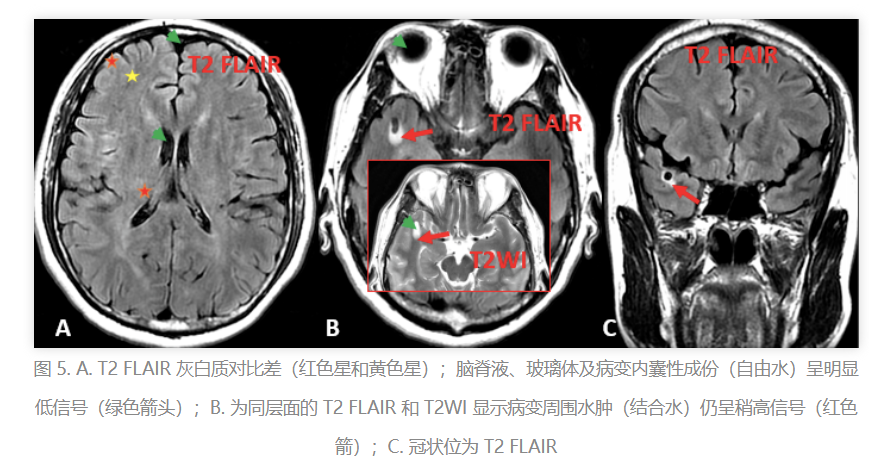

FLAIR:专门压制脑脊液的信号,就像是给大脑拍了一张“去水印照”,让病灶更加清晰。

FLAIR:脑脊液变黑了,病灶更清晰了,像是一张去除杂质的照片。